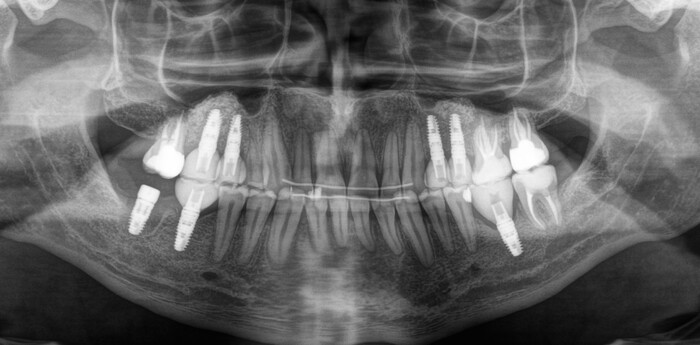

После недолгой беседы и осмотра

Роману было предложено сделать компьютерную томографию для более детальной диагностики и составления комплексного плана лечения.

На снимке видно, что он следил за зубами, занимался лечением, но в определенный момент что-то пошло не так. После проведения совместной консультации со всеми смежными специалистами (ортодонтом, ортопедом, терапевтом) пациенту был предложен комплексный план лечения, который включает в себя:

После удаления, лечения и начала ортодонтии прошло около 8 месяцев:

Кривые зубы раскривились, заваленные – распрямились.

После того, как все активные передвижения зубов закончены, ортодонт даёт отмашку для начала установки имплантатов.

Было принято решение начать с правой стороны:

Произведена установка 3 имплантатов и синус-лифтинг в области 5-го и 6-го зуба на верхней челюсти и 6-го на нижней. В полости рта это выглядело примерно так:

Спустя примерно 3 месяца пришла очередь левой стороны:

Также были установлены 2 имплантата и проведен синус-лифтинг на верхней челюсти (в области 5-го и 6-го зуба) и 1 на нижней (в области 6-го зуба).